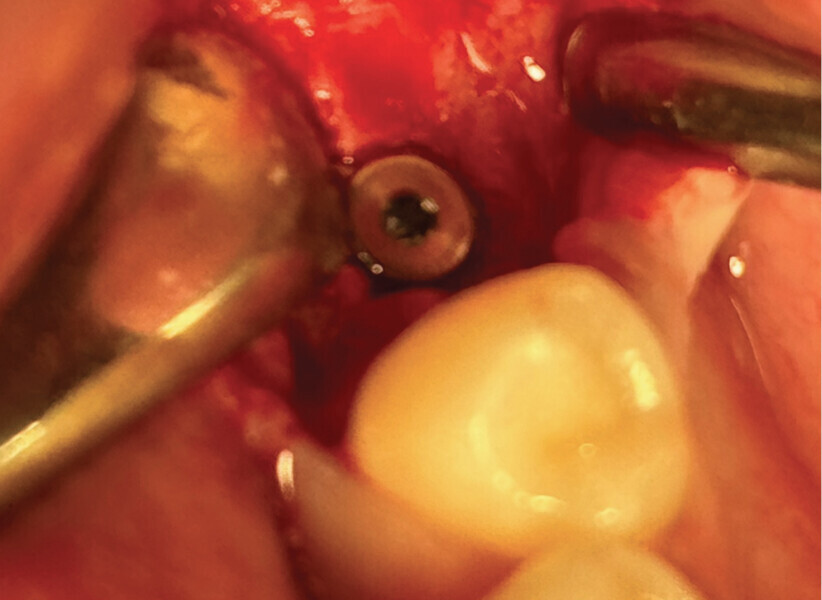

Fig. 2

C’est sa structure et composition spécifique qui va permettre la non-compétition cellulaire et par la même la constitution de l’os sous la membrane. Les cellules épithéliales vont, quant à elles, se développer en tapissant la surface lisse de cette membrane (Figs. 2 et 3).